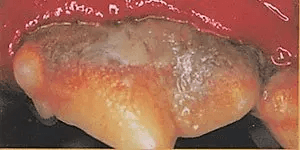

The veterinarian recommended a dental evaluation and cleaning for this pet. The tartar is causing infection of the gums, as evidenced by the redness and swelling above the tooth.